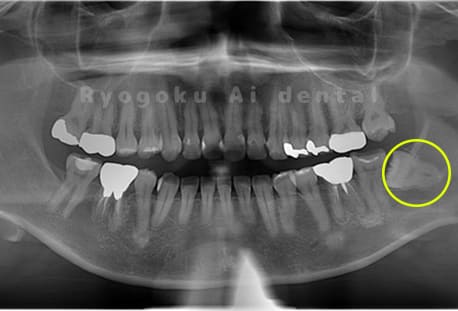

- 下顎左の水平埋伏智歯

-

- 治療内容

- 下顎左の水平埋伏智歯を抜歯したケースです。

<リスク・副作用>

手術後は痛み、腫れ、痺れなどの副作用が生じる場合があります。